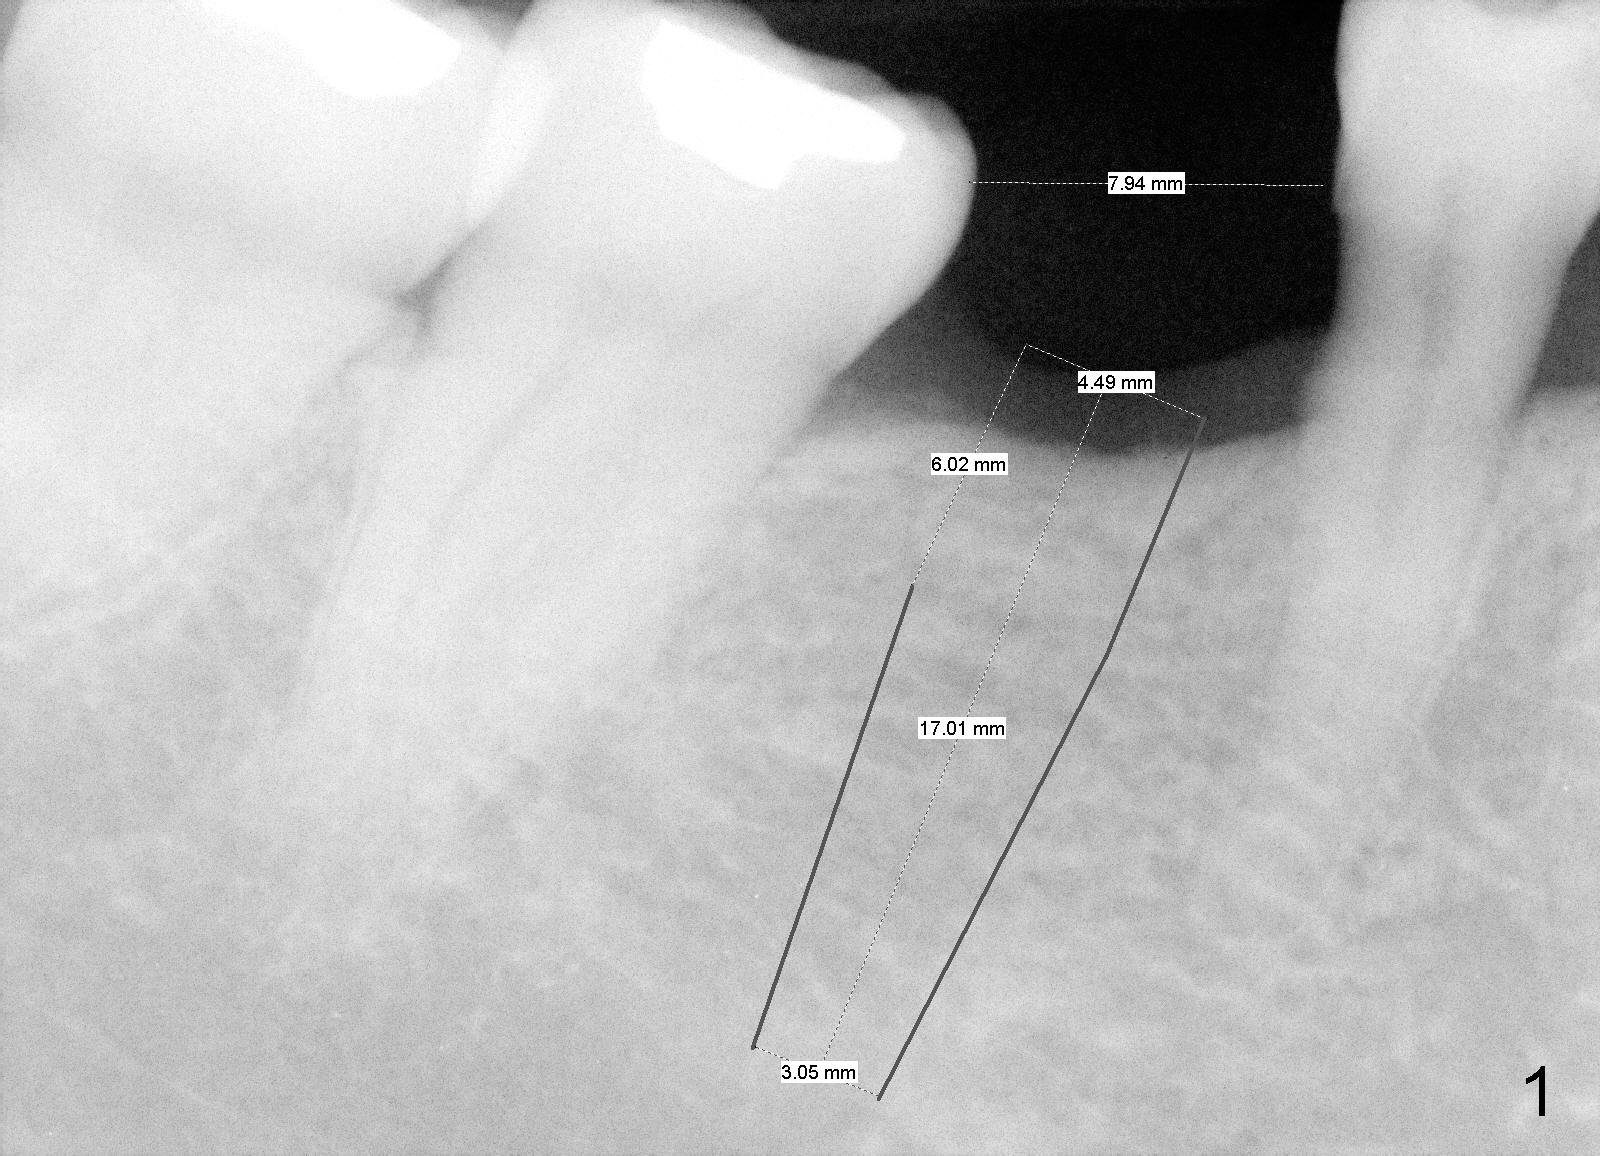

Due to unavailability of bone-level implant, a tissue-level implant is to be placed as a backup (Fig.1: 4.5x17 mm). Osteotomy is initiated with 1.5 mm pilot drill at depth of ~ 10 mm; the trajectory appears to be as good as expected (Fig.2). Osteotomy is gradually increased to 4.5x17 mm, followed by insertion of 4.5x17 mm tap (Fig.3,4). The ostetomy appears to be deviated lingual (Fig.5). When the tap is removed, the buccal plate appears to be thin (Fig.6). A tapered implant is placed (Fig.7).